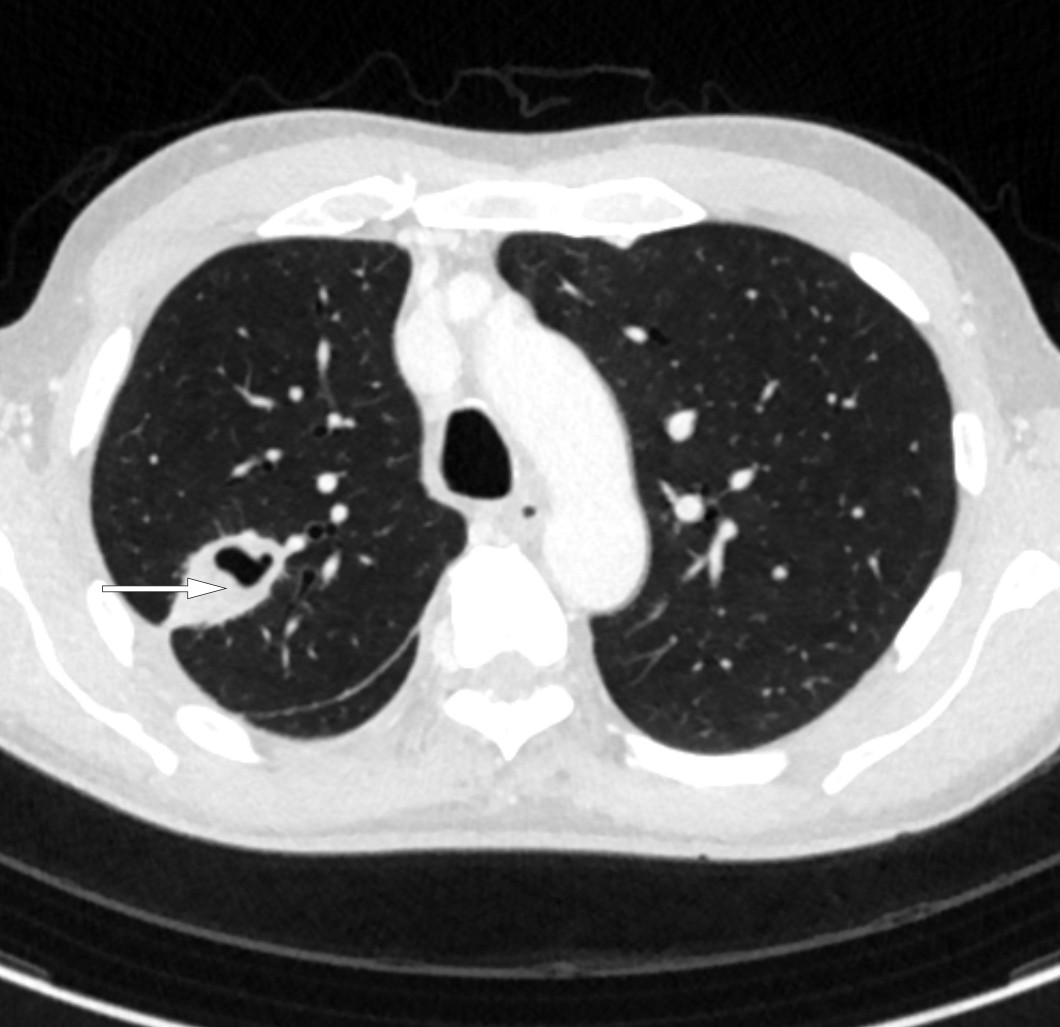

På sykehuset var allmenntilstanden god. Blodtrykket var 168/84 mm Hg, puls 85 slag per minutt, temperatur 37,8 °C i øret, perifer oksygenmetning 97 % i romluft og respirasjonsfrekvens 20 per minutt. Han hadde en systolisk bilyd grad 1 over hjertet, best hørbar i andre høyre interkostalrom, og basalt over høyre lunge var det svekket respirasjonslyd med perkutatorisk dempning. Han hadde ingen cyanose, lymfeknutesvulst, fortykkelse av fingre og tær (clubbing), urglassnegler, palpabel hepatosplenomegali, eksantemer eller perifere ødemer. Blodprøvene viste CRP 105 mg/L og albumin 34,4 g/L (35–45 g/L). Hematologiske prøver, elektrolytter, nyre-, lever- og galleprøver var alle innenfor normale grenser. Røntgen thorax (figur 1) viste flere delvis konsoliderte fortetninger, særlig i nedre del av høyre lunges overlapp, atelektasestriper og høyresidig pleuravæske. Mengden var for liten for drenasje. Basert på sykehistorien med tørrhoste, pneumonisuspekte fortetninger på lungerøntgen og moderat forhøyet CRP uten leukocytose, ble tilstanden oppfattet som en atypisk pneumoni. Pasienten ble utskrevet etter ett døgn med azitromycintabletter 500 mg daglig i tre dager. Azitromycin ble valgt til fordel for erytromycin på grunn av økt intracellulær konsentrasjon, økt sannsynlighet for etterlevelse og erfaringsmessig mindre sannsynlighet for gastrointestinale bivirkninger.

CT thorax (figur 3) to dager etter innleggelse viste basalt i høyre lunges overlapp en konsolidert fortetning med sentral luft, en kaverne, med største diameter 58 mm. Ved siden av denne var det tre-i-knopp-forandringer og flere mikronoduli. Pleurahinnen rundt pleuravæsken var fortykket med økt kontrastoppladning med inntilliggende fortetninger både i underlapp og midtlapp. Noen lymfeknuter i høyre hilus og mediastinum var forkalket og større enn normalt. Apikalt medialt i venstre lunges overlapp var det en mindre irregulær fortetning på rundt 1 cm med omkringliggende små mikronoduli, men ingen pleuravæske. Det ble stilt spørsmål om fortykket perikard.